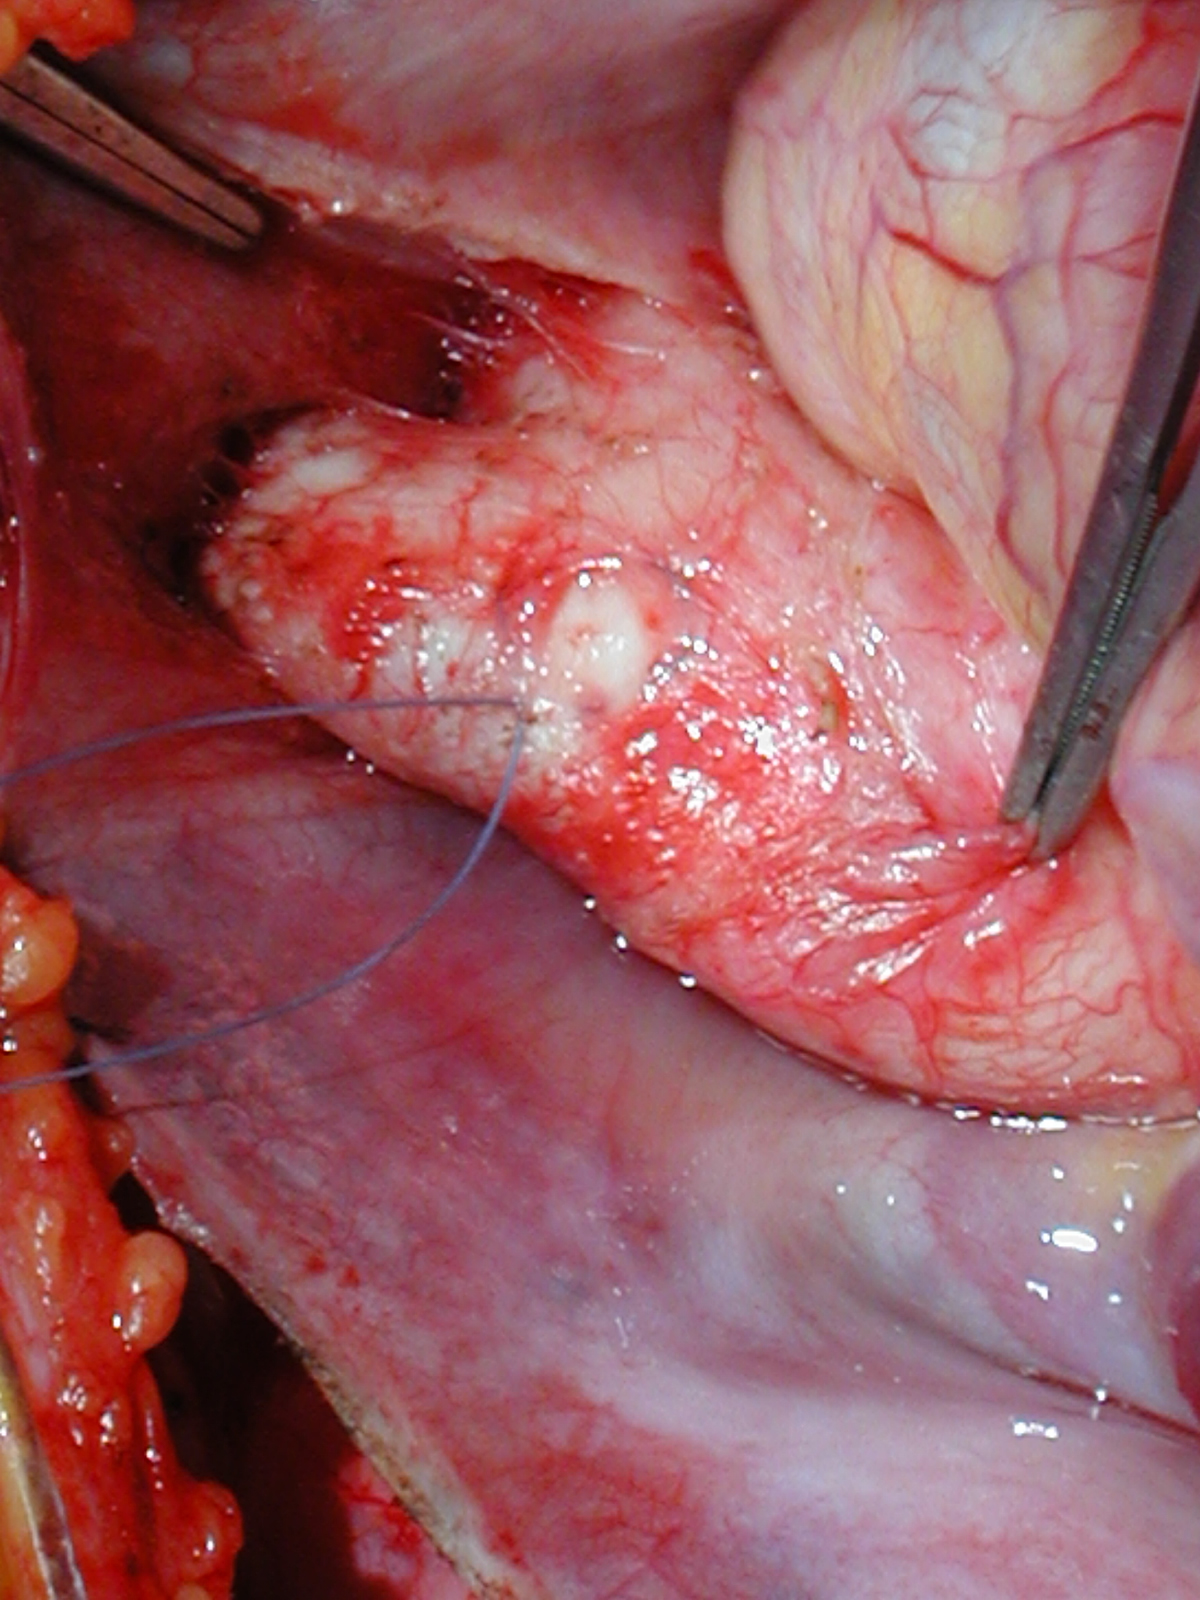

Figures 28 & 29: Completed noncoronary cusp patch. Figure 30: A portion of thick intimal hyperplasia adjacent to the left coronary orifice is sharply resected with a no. 11 blade. Figure 31: Completed resection showing no residual intimal thickness.

Figure Figure Figure Figure